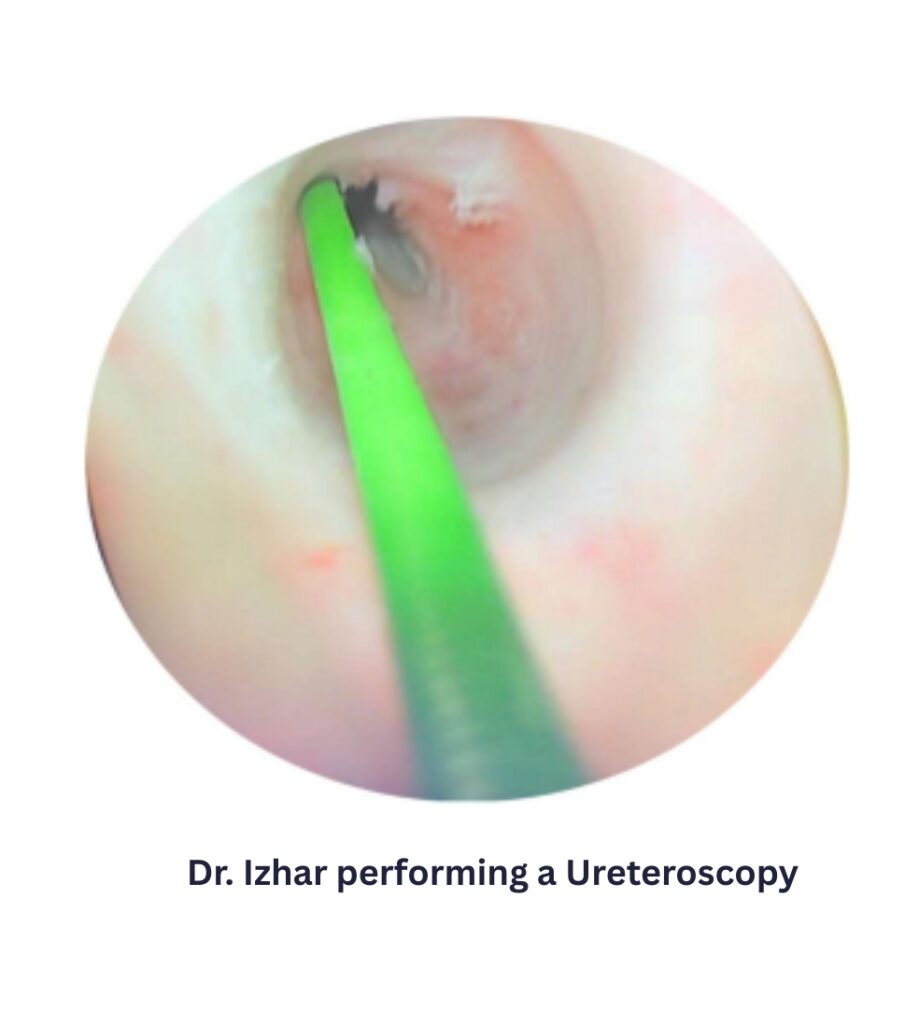

Bukhari Medical supports modern urological surgery with innovative medical technologies. Our solutions enable surgeons to perform efficient and minimally invasive procedures for conditions such as BPH, kidney stones, and other urological disorders.

Minimally invasive procedures such as laparoscopy and ureteroscopy have transformed modern surgical practice. These techniques use smaller incisions and advanced visualization systems, allowing surgeons to perform procedures with greater precision while reducing tissue trauma, bleeding, and recovery time. Bukhari Medical supports these procedures with reliable medical technologies designed to enhance surgical efficiency and clinical performance.

Urology:

Kidney surgery

Prostate surgery

Ureteral procedures